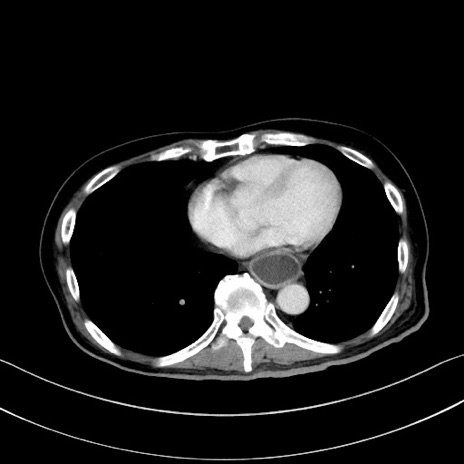

冠状断像

【症例】60歳代男性

【現病歴】胃癌にて胃全摘後。食思不振が悪化し、夜中に嘔吐することがある。

【既往歴】胃癌、胃全摘、脾摘、胆摘後